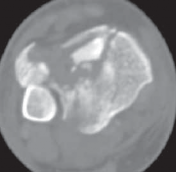

22.

Cole et al3 mapped 38 consecutive AO/OTA 43-C3 (complex articular) plafond fractures with CT scans and found that all plafond fractures in this category exited the tibiofibular joint laterally and at two separate locations medially to create a coronally oriented Y pattern with three major fragments ( FIG 2A). There were also varying amounts of articular comminution anterolaterally or anteromedially (FIG 2B).

--- A B ### FIG 2 • A,B. CT images from 43-C3 plafond injuries demonstrating typical fracture patterns with anterolateral, medial malleolus, and posteromedial fragments. Variable amounts of central or anterocentral articular impaction and comminution are commonly seen.

1. Isolated osteochondral fragments of variable size are often encountered (typically central to anterolateral in location; Fig 2B) and constitute the remaining portion of the articular surface.